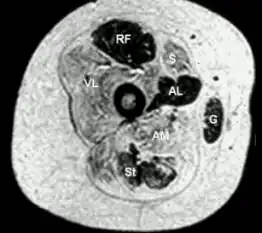

- Transverse section from child with central core disease

- Histopathologic appearance of typical central core disease: NADH-TR, transverse section from the rectus femoris. Marked predominance of dark staining, high oxidative type 1 fibres with cores affecting the majority of fibres. Cores are typically well demarcated and centrally located (→), but may occasionally be multiple and of eccentric location.

The diagnosis is made based on the combination of typical symptoms and the appearance on biopsy (tissue sample) from muscle. The name derives from the typical appearance of the biopsy on light microscopy, where the muscle cells have cores that are devoid of mitochondria and specific enzymes.[2]